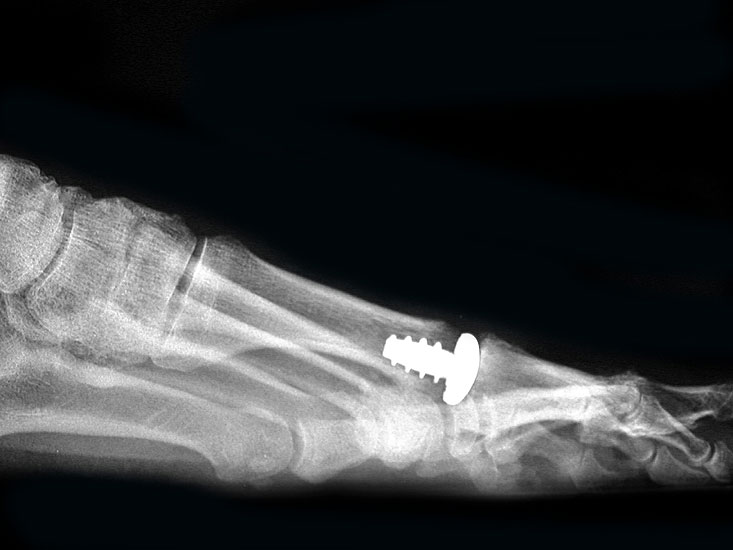

Resultate:

Die ersten Versuche mit der Prothetik am Großzehengrundgelenk wurden mit metallischen Hemi-Implantaten (Abb. 13, 14) vorgenommen. Eine Studie 47 mit größerem Kollektiv im Langzeitverlauf zeigte befriedigende Resultate, trotzdem hat sich die Technik bis heute nicht wirklich durchgesetzt. Der gleiche Autor verglich die Endoprothese mit der periartikulären Osteotomie und konnte keine wesentlichen Unterschiede feststellen 48. Eine neuere Studie vergleicht die Hemiarthroplastik mit der Arthrodese und der Resektionsarthroplastik und kann keine signifikanten Unterschiede feststellen 49. Metall–Polyäthylen-Paarungen zeigten eine hohe Lockerungsrate der Komponenten, weshalb sich diese Paarung ebenfalls nicht durchsetzte 505152. Am meisten Erfahrung besteht mit der Silikonprothese. Initial als Hemiprothese propagiert 46, wurde wegen mangelhaften Erfolgen 5354 die Totalprothese mit zwei Schäften eingeführt 55. Die Langzeitergebnisse sind widersprüchlich 55565758 so dass wegen der Verunsicherung dieses Model aktuell nicht regelmässig zum Einsatz kommt.